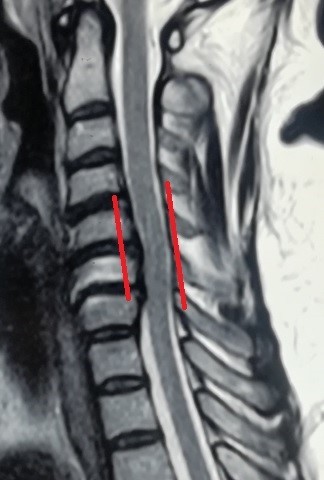

انزلاق غضروفي عنقي متعدد قبل وبعد الجراحة

versatile herniated disc before surgery

An image of an MRI scan of a 47-year-old patient suffering from partial quadriplegia due to multiple cervical disc herniation from the fourth cervical vertebra to the seventh. As shown in red, the location of the slip and the size of the effect resulting from pressure on the cervical spinal cord. And the image shaded in green after a surgical microscope surgery to remove the cartilage from the front and install alternative cervical cages after four months of surgery, as it shows the marrow liberation from pressure, which reflected on the patient's condition improvement.